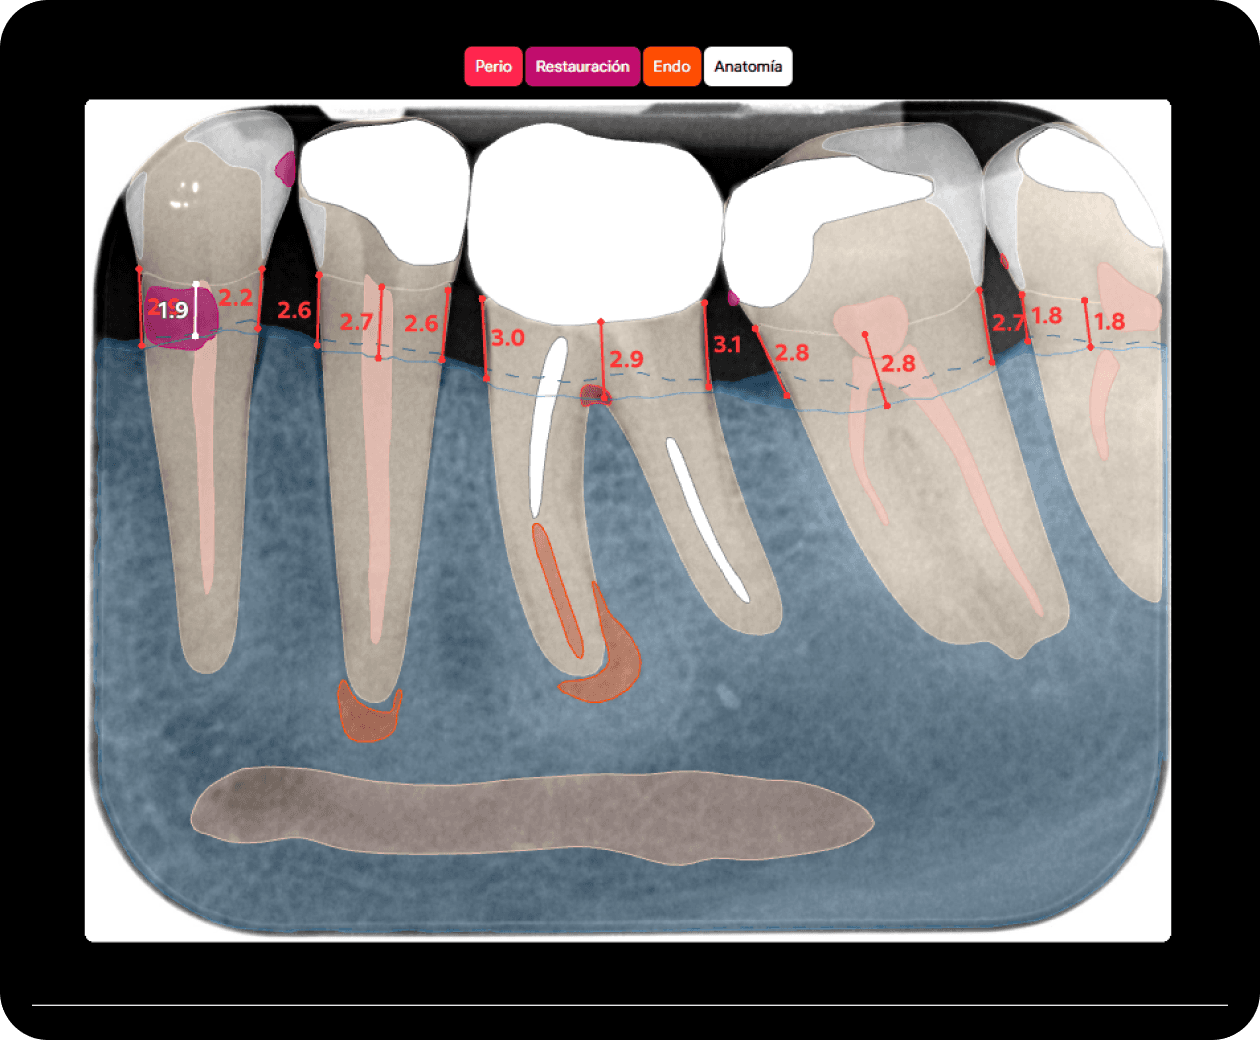

Diagnocat analiza imágenes radiológicas, simplifica la comunicación médico-paciente y motiva al paciente a iniciar el tratamiento.

Diagnocat simplifica las consultas iniciales, optimiza el trabajo en equipo y proporciona informes analíticos para la gestión.